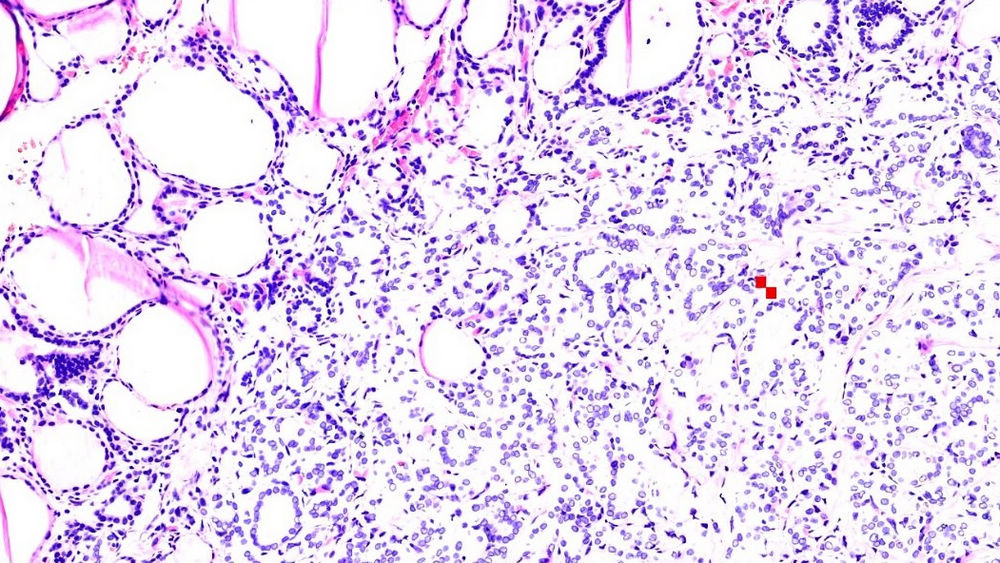

小土豆跟着农人老师学本领-食道手术切除 粘膜表面鳞状上皮缺乏异型性 基底部细胞排列紊乱 浸润性生长  鳞癌